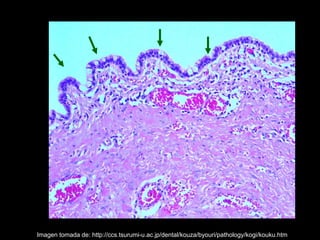

El quiste nasopalatino es un quiste embrionario situado en la línea media en la parte anterior del paladar, que se origina de los restos del conducto nasopalatino. Generalmente aparece entre los 40-60 años y se presenta como un aumento de volumen blando y no doloroso entre los incisivos centrales superiores que puede causar divergencia radicular. Las características radiográficas incluyen una lesión radiolúcida, bien delimitada y de forma redondeada u ovalada que cruza la línea media maxilar.